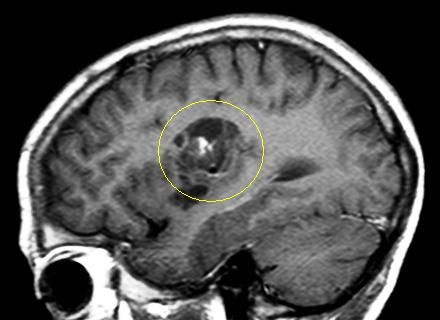

Es handelt sich um ein bildgebendes Verfahren, bei dem die Patienten in einer Röhre liegen und währenddessen mit Hilfe von wechselnden Magnetfeldern nach einem speziellen Epilepsie-Protokoll Bilder des Gehirns gemacht werden. So können Tumoren, Fehlbildungen oder andere Veränderungen des Gehirns, die Anfälle verursachen können, sichtbar gemacht werden. Durch moderne computergesteuerte Nachbearbeitungsmethoden oder Überlagerung mit anderen Bildmodalitäten können Läsionen dann noch besser dargestellt werden.

Folgende Veränderungen oder Erkrankungen des Gehirns werden häufig und mit gutem Erfolg (70-80% Anfallsfreiheit) epilepsiechirurgisch behandelt:

Tumoren

Hippocampussklerose

Fokale

cortikale Dysplasie

Umschriebene Fehlbildungen der Hirnrinde